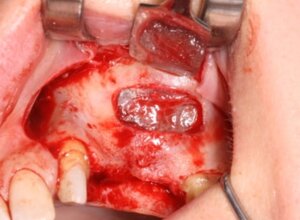

Chirurgia Maxillo-Facciale: gestione degli interventi complessi e riabilitazioni avanzate.

Implantologia Guidata: chirurgia mini-invasiva di alta precisione.